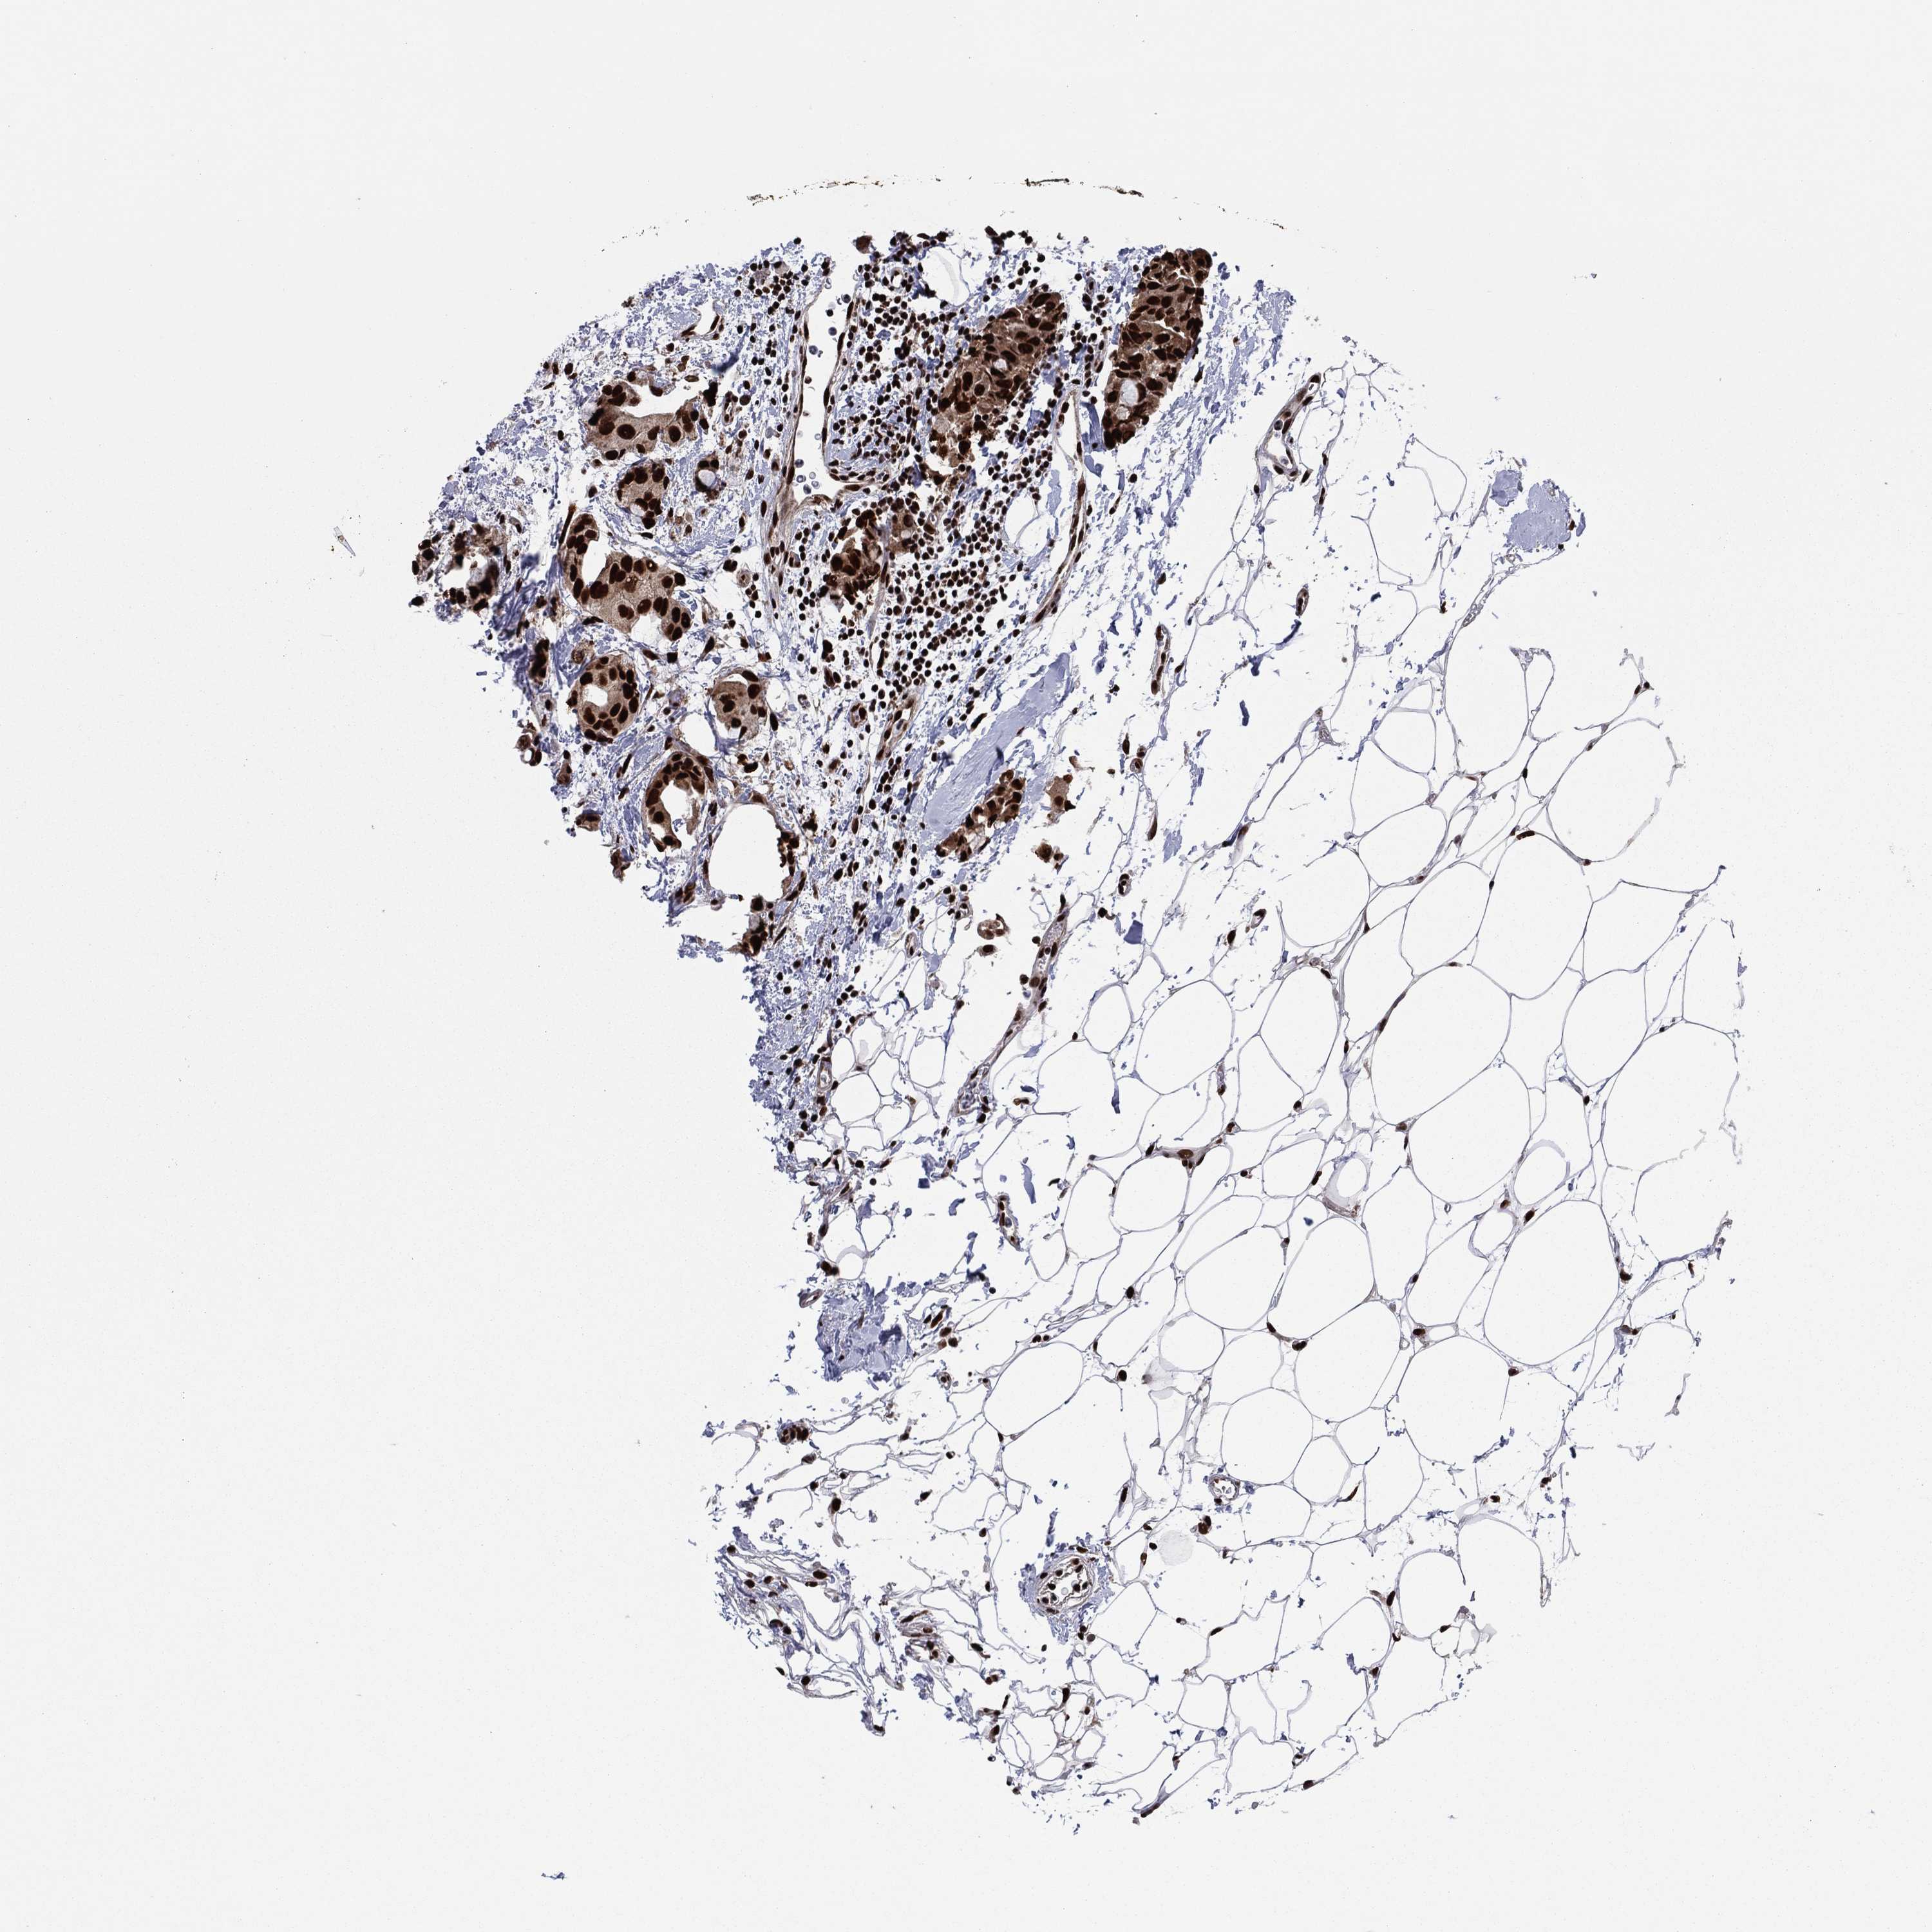

CANCER BREAST CANCER Show tissue menu

BRCA TCGA BRCA VALIDATION PROTEIN EXPRESSION